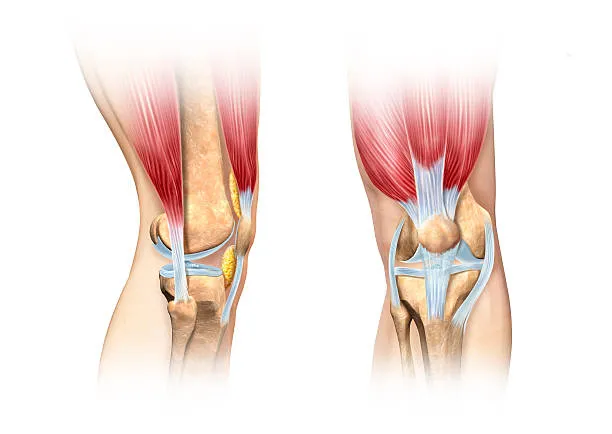

첫 번째는 근육 및 인대의 손상

과도한 사용이나 부상으로 인해 근육이나 인대가 늘어나거나 찢어지는 경우가 있습니다. 이러한 손상은 단순한 통증뿐만 아니라 부기, 멍이 듦, 움직임의 제한 같은 다른 증상들을 동반할 수 있습니다. 이 상황에서의 치료는 대개 휴식, 냉찜질, 압박 붕대 사용, 부위를 높게 유지하는 것과 같은 자가 관리 방법과 필요에 따라 진통제 또는 스테로이드 주사와 같은 의학적 치료로 구성됩니다.

두 번째는 연골 손상

무릎 관절 사이에서 뼈와 뼈의 마찰을 줄여주는 부드러운 조직인 연골이 관련되어 있습니다. 나이 증가, 과체중, 관절염 등으로 인해 연골이 닳거나 소실되면, 뼈 사이의 직접적인 마찰로 인해 통증이 발생할 수 있으며, 이로 인해 움직임의 제한, 삐걱거리는 소리, 염증과 같은 증상이 나타날 수 있습니다.